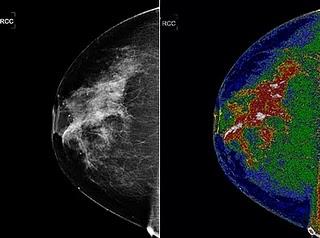

Un 'software' de la NASA creado para mejorar las imágenes de la Tierra tomadas por los satélites podría ayudar a interpretar pruebas de imagen médicas como mamografías, ecografías, etc. El sistema impulsaría el diagnóstico precoz de enfermedades como el cáncer.

Con este nuevo instrumento, los profesionales "pueden utilizar el sistema MED-SEG para separar las imágenes de dos dimensiones en secciones relacionadas digitalmente o regiones que, después de la coloración, puede ser etiquetados individualmente por el usuario", detalla el presidente de Bartron, Fitz Walker.

Uno de los primeras aplicaciones del sistema MED-SEG, que empezará a usarse en ensayos clínicos en los próximos meses, será mejorar la mamografía. Así lo espera Molly Brewer, profesora de la División de Oncología Ginecológica de la Universidad de Connecticut, que confía en que la nueva técnica será herramienta útil para diagnosticar el cáncer de mama, reduciendo los sesgos.

Para la doctora, "la precisión del MED-SEG permite al médico ver muchos más detalles y de mejor calidad lo que podría ahorrar a los pacientes una gran cantidad de pruebas costosas e innecesarias".